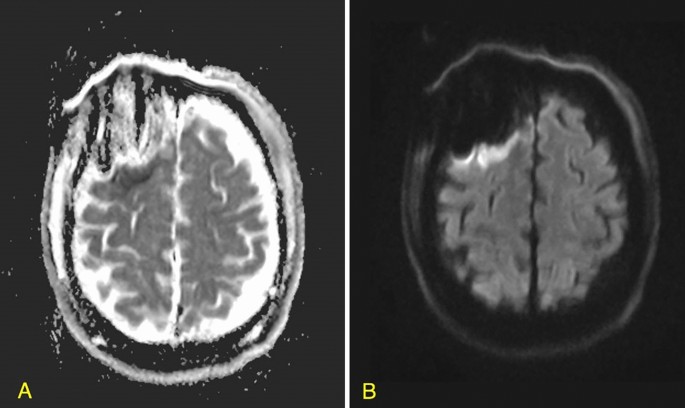

Radiological data

Data on tumor volume and location, tumor enhancement, and extent of resection (EOR) were derived from pre- and immediate postoperative MRI studies, which are routinely performed within 48 h after surgery.3,16 . The EOR for GBM and LGG was calculated using the following formula: (preoperative − postoperative tumor volume)/preoperative tumor volume × 100). In case of GBM, the volume of blood products rather than the volume of the residual tumor was confirmed by comparing T1-weighted gadolinium-enhanced and non-enhanced MRIs. FLAIR sequence was used for measuring the non-enhancing component of the tumors17. Rim-pattern restriction surrounding the resection cavity was detected by a neuroradiologist who was blinded to clinical outcomes, and it was based on DWI studies and apparent diffusion coefficient techniques (Fig. 1). Infarcts, which were excluded from this study, were distinguished by their typical wedge-shaped arterial territory and relatively rapid appearance on immediate post-op DWI. Areas of T1-weighted hyper-intensities, accompanied by areas of hyperdensity on post-operative computerized tomographs (CT) were considered as blood products11,14.